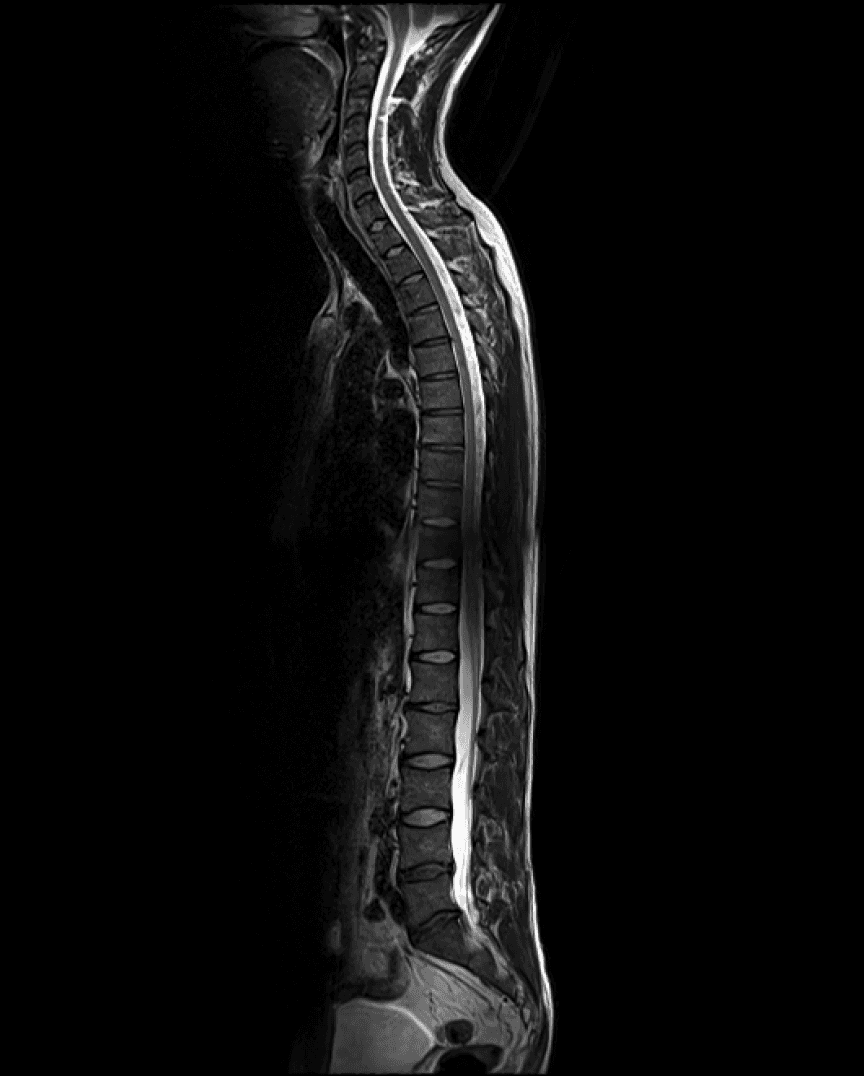

Your recent health check-up provides a detailed overview of your health, showing some very positive developments alongside a few areas that warrant attention. The most notable findings are related to age-appropriate wear-and-tear in your spine.

AI-based annotation of your body

Easily understand highly technical scans.

Side-by-side comparison

Track internal changes over the years.

Additional insights

Background information on biomarkers and imaging results.